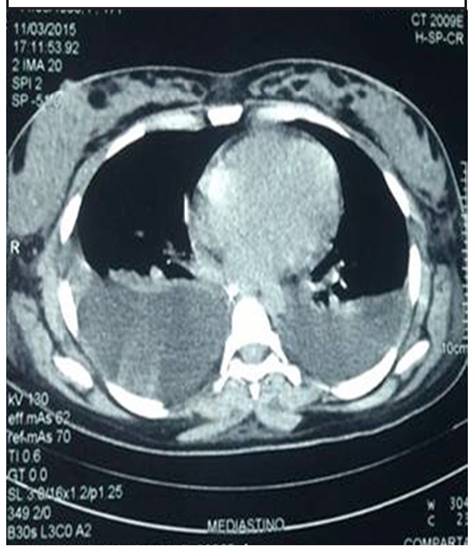

Al sexto día, continúa en disfunción orgánica múltiple con compromiso renal severo, oligúrica, acidosis metabólica y con sobre carga hídrica. Se logra controlar la coagulopatía, pero persiste con signos claros de hemólisis intravascular, dados por LDH en incremento persistente pese al manejo médico instaurado y trombocitopenia en progresión. Se realiza TAC de tórax (figura 1), encontrando derrame pleural bilateral y presencia de ascitis severa. Endoscopia de vías digestivas altas realizada no demostró sangrado digestivo pese a anemización persistente. Paraclínicos de control: Plaquetas: 67000mm, Creatinina: 2,5, BUN: 96,TGO: 103,TGP: 33,BT: 12,Triglicéridos: 1354, HB: 8.